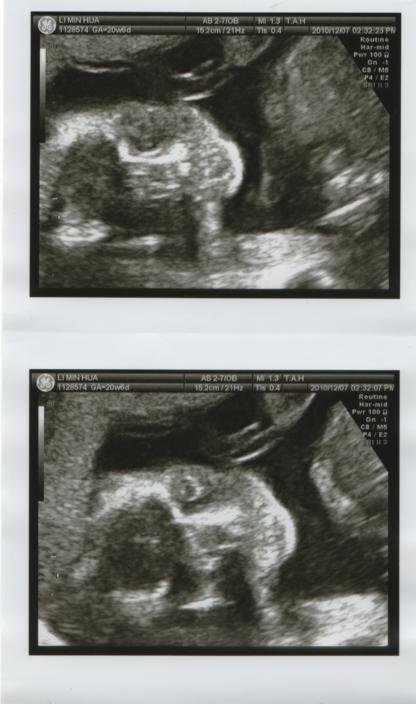

高層次超音波只有這樣的照片?!

今天到醫院做了高層次超音波,因為寶寶姿勢不好→翹屁股趴著

半小時結束後拿到這樣四張臉部照片,其餘的手腳、大腿、小腿的照片都沒有

若是這樣應該也要提供不一樣的部位吧?!跟醫生反應得到的答案是"姿勢不好"?所以只提供照的清楚的臉...

今天的高層次超音波,在半小時快速講解中結束了,拿到了這樣4張照片

結果拿到的只有這四張高層次"臉部特寫"大頭照...因為看到的都是骨骼,感覺還挺像外星人的說....